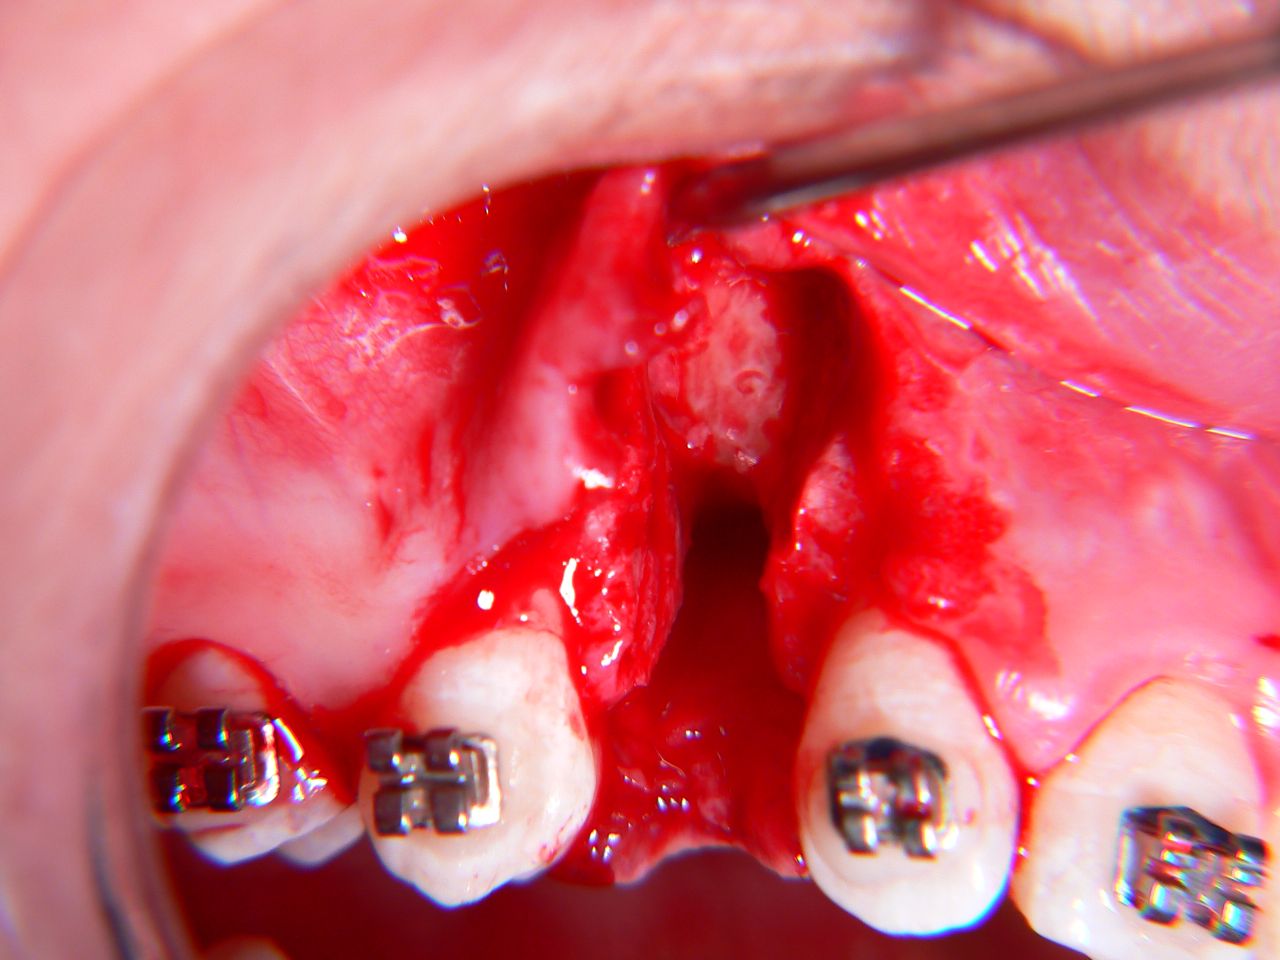

ESTRAZIONE CANINO INCLUSO PALATALE – Dott. Pier Francesco Amoroso

ESTRAZIONE CANINO INCLUSO PALATALE – Dott. Pier Francesco Amoroso from www.dottoramoroso.it

Estrazione Canino Incluso Fa Male. Estrazione Canino Incluso Fa Male, Canino incluso nel palato estrazione dentale, 1.33 MB, 00:58, 1,662, Augusto Arrighi, 2022-04-30T05:31:38.000000Z, 3, ESTRAZIONE CANINO INCLUSO PALATALE – Dott. Pier Francesco Amoroso, www.dottoramoroso.it, 600 x 608, png, WebNel video i passaggi dell'estrazione di un canino incluso. La procedura viene eseguita in anestesia locale. ← Post meno recente. Post più recente →. Condividi.., 20, estrazione-canino-incluso-fa-male, Notizie e vestiti